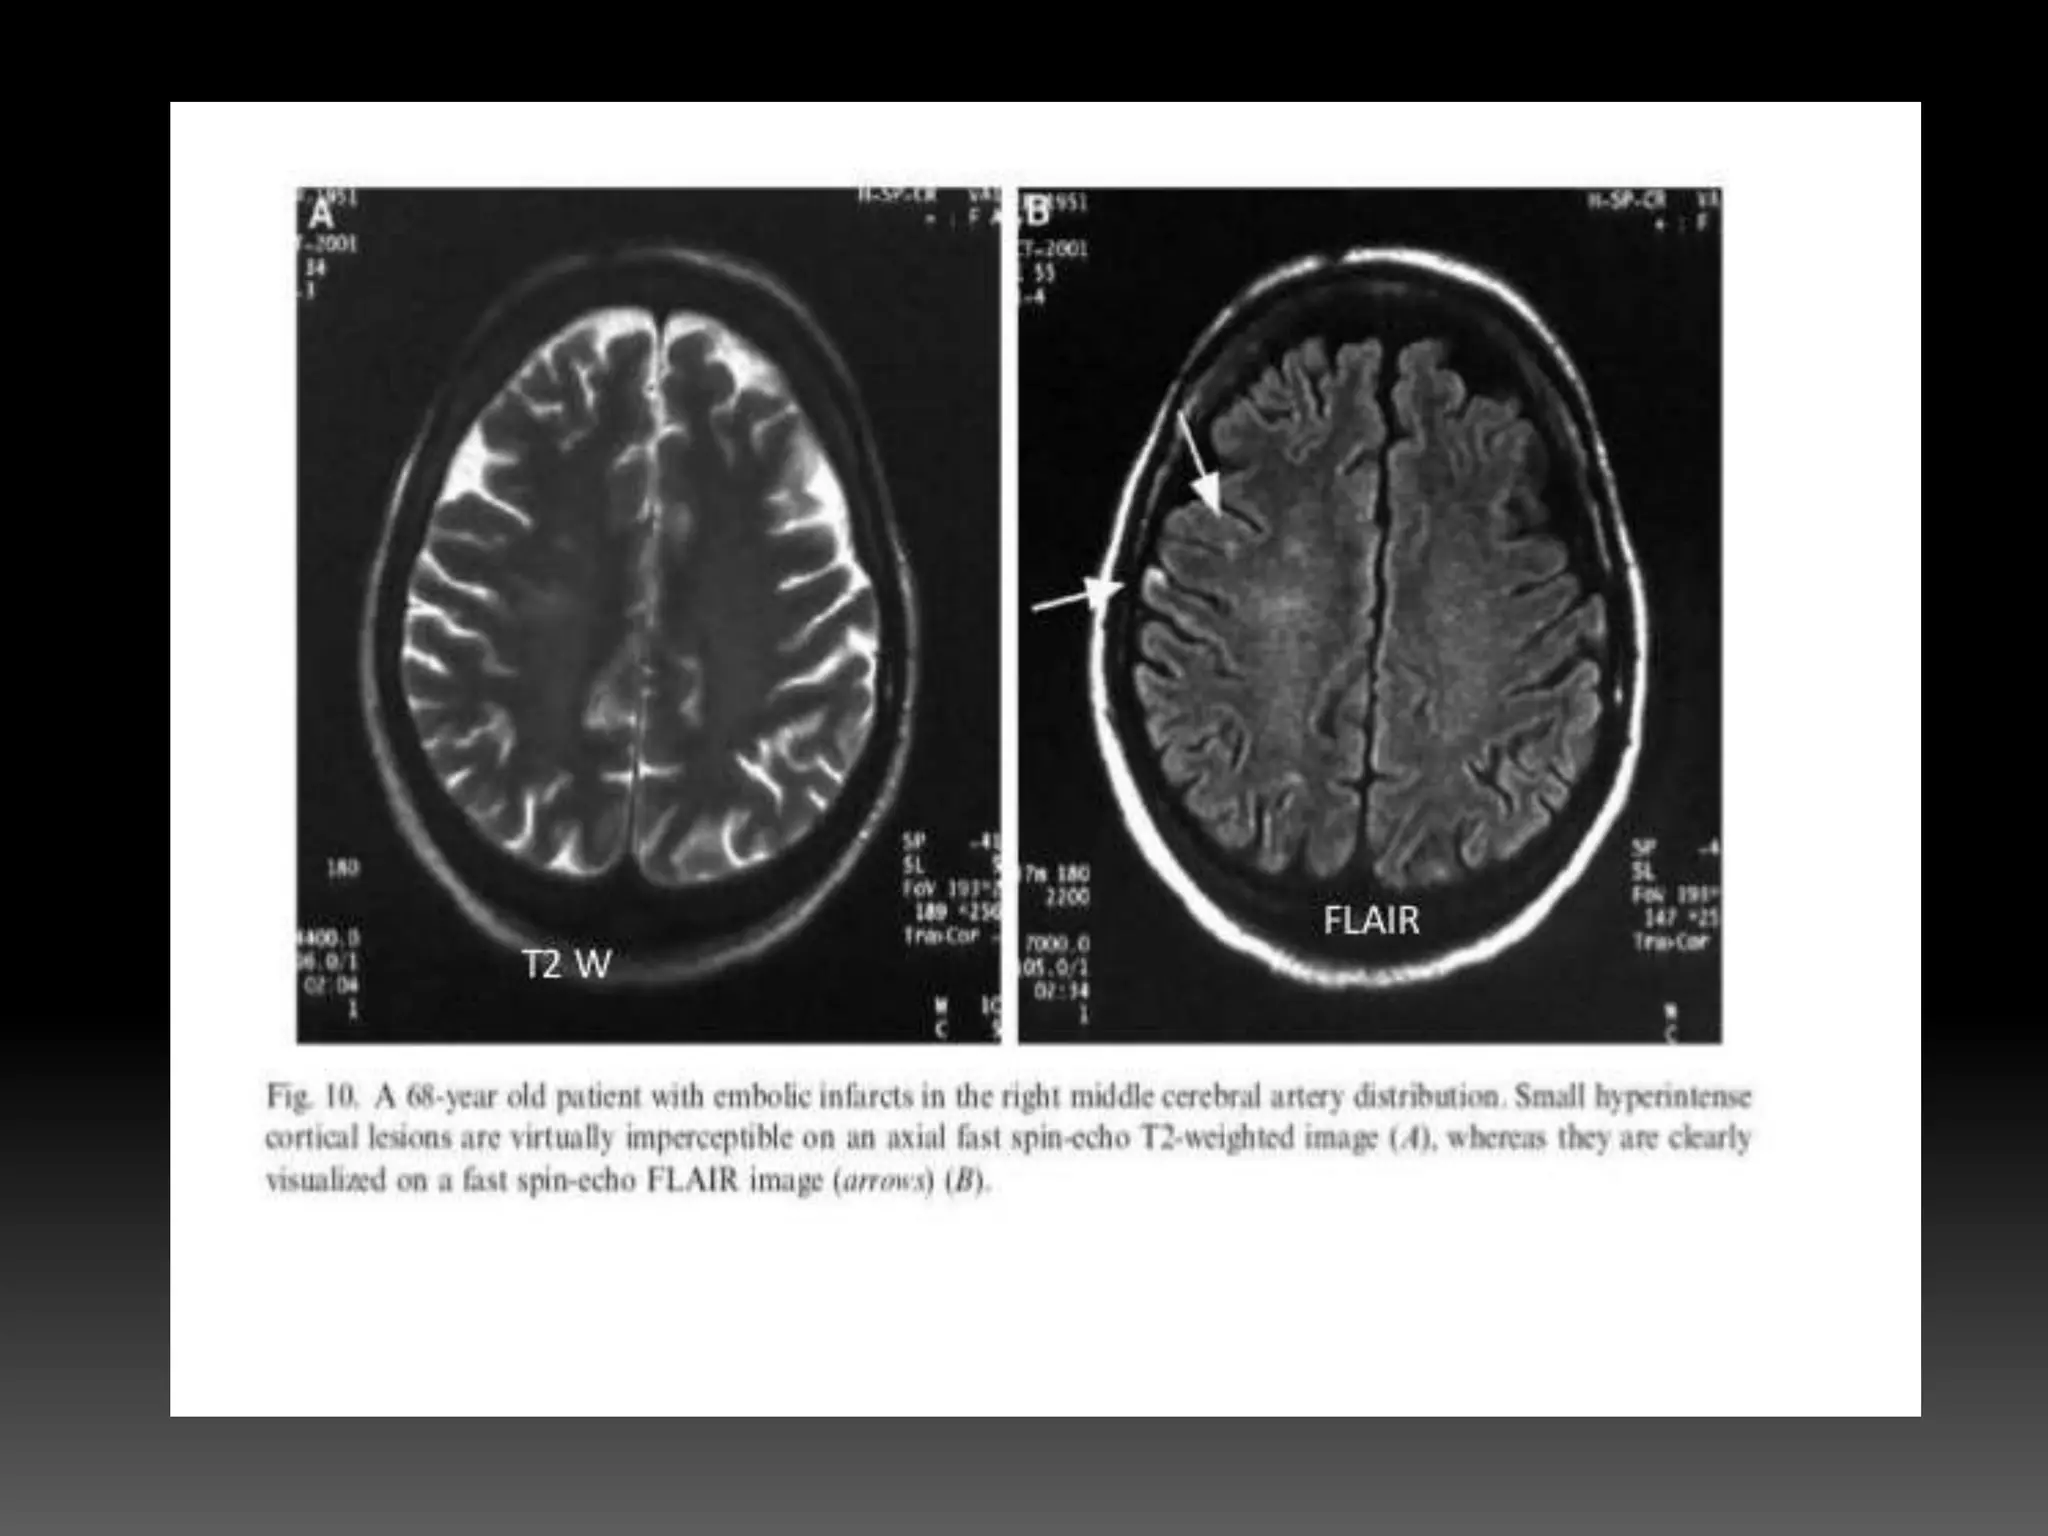

T2 weighted image •Differences in the T2 times between fat and water • To achieve T2 weighting, • TE must be long enough(60 ms or more) to give both fat and water time to decay. Long TR times(2000 ms) • If the TE is too short, neither fat nor water has time to decay, and therefore the differences in their T2 times are not demonstrated

• Tissues withlong T2 times – CSF or temporomandibular (TMJ) joint Fluid - appear bright • Tissues with short T2 times – Fat - appear dark. • Most commonly used for identifying inflammatory or other pathologic changes.